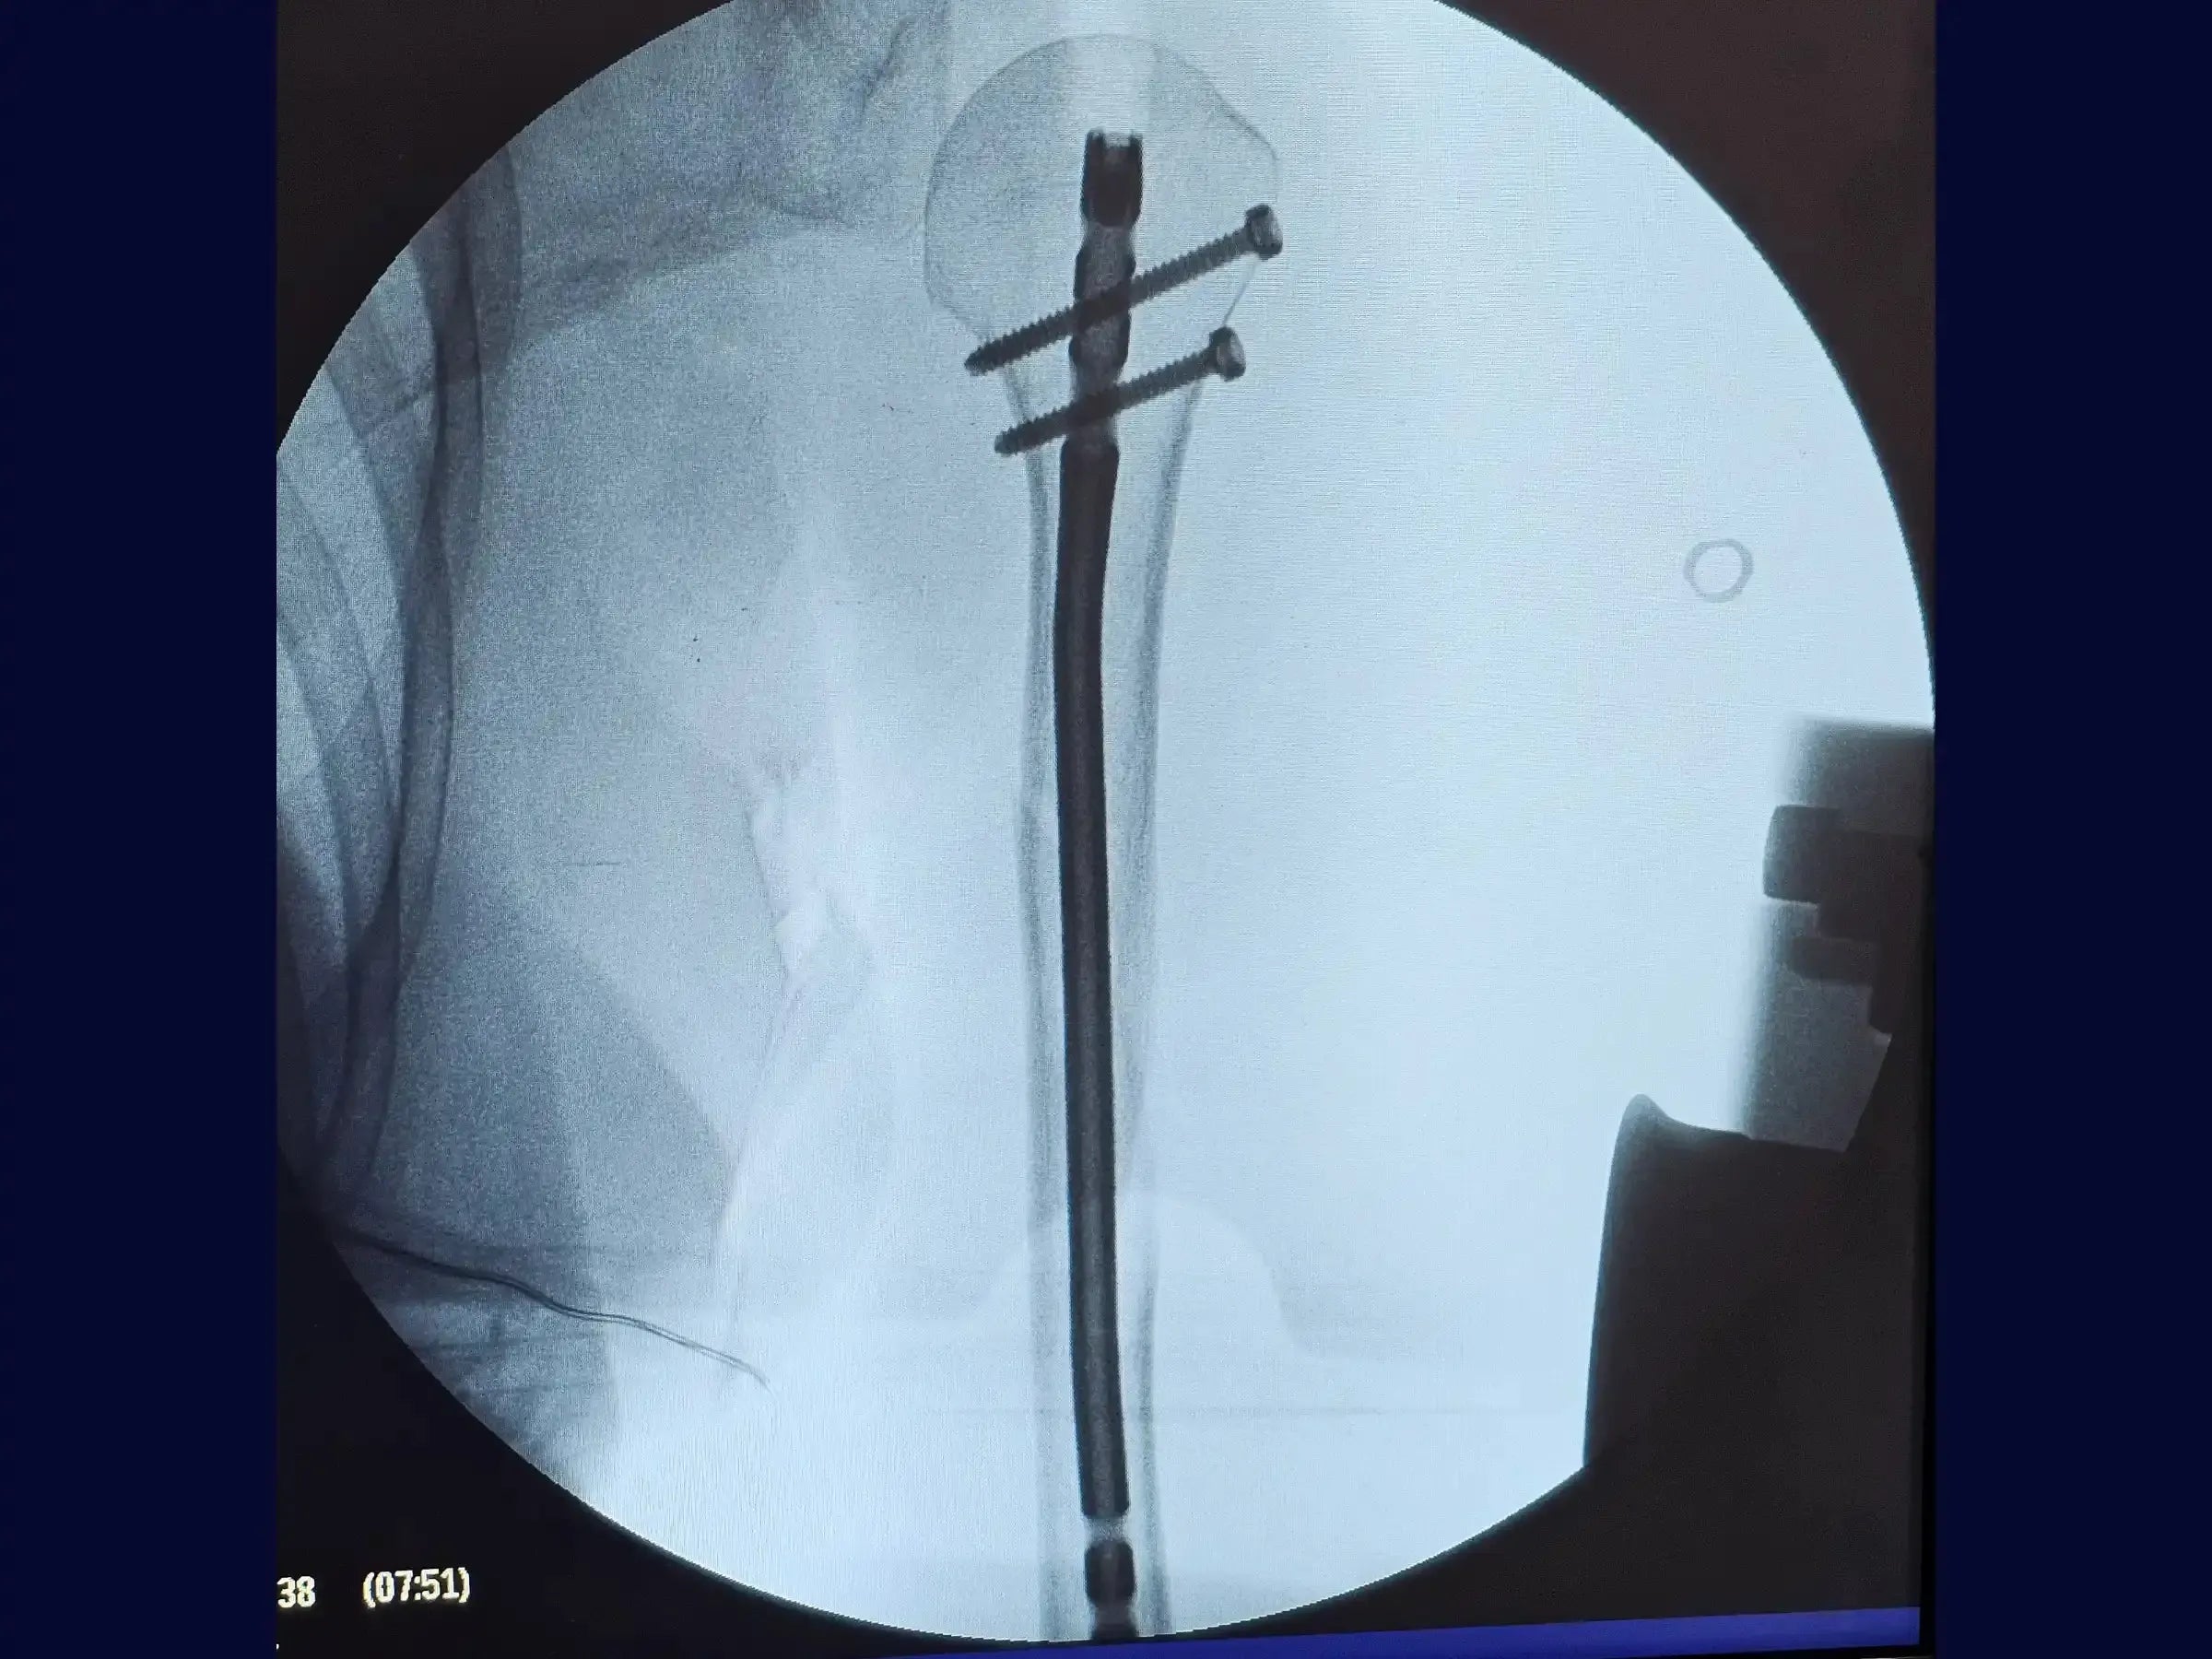

- Intramedullary nail fixation technique.

- Measurement and Insertion of the Intramedullary Rod: Develop the skill to measure the intramedullary rod accurately, considering the triangular tapering of the medullary canal to avoid protrusions and optimize the fit of the implant.

- Proximal Blocking Techniques: Master the creation of proximal blocks, using oblique screws directed to the humeral calcar to ensure the fixation of the stem.

- High Difficulty Distal Blocking: Delve into the freehand distal blocking technique, a challenging procedure due to the triangular anatomy of the distal humerus. Understand the importance of using a sharp-tipped drill to avoid slippage and ensure the precision of the one-centimeter incision.